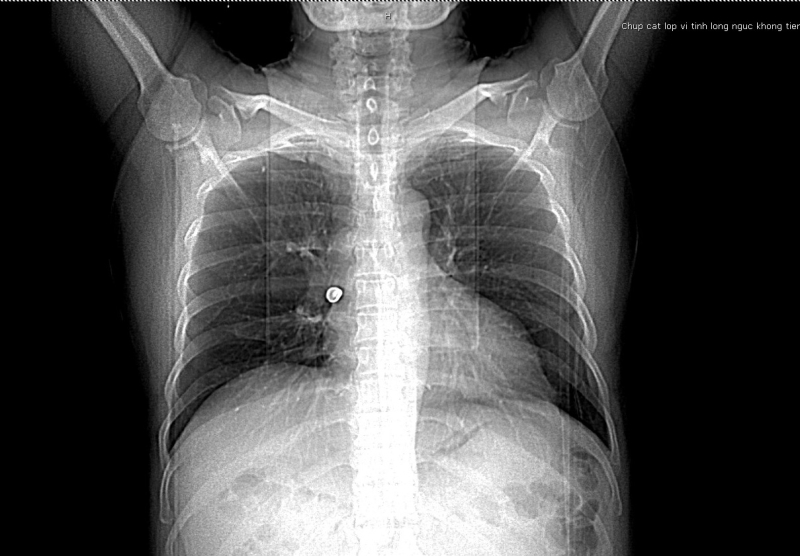

Trước nhập viện bệnh nhân bị ho sặc, tức ngực, khó thở. Tại Bệnh viện Bãi Cháy, bệnh nhân được thăm khám lâm sàng, thực hiện các xét nghiệm, chẩn đoán hình ảnh. Kết quả chụp CT scanner lồng ngực phát hiện vị trí phế quản phải có hình ảnh dị vật phản quang kích thước 17x12mmm. Các bác sĩ đã hội chẩn chuyên khoa hô hấp và chỉ định can thiệp nội soi phế quản để gắp dị vật.

Quá trình nội soi lòng phế quản, ekip can thiệp của Khoa Nội Hô hấp, Bệnh viện Bãi Cháy phát hiện một chiếc răng giả rơi vào gốc phế quản phải, vị trí tiếp cận lấy dị vật rất khó khăn . Tuy nhiên với sự hỗ trợ của các trang thiết bị nội soi hiện đại, các bác sĩ đã gắp thành công dị vật, hút rửa sạch phế quản cho người bệnh. Sau can thiệp 24h, bệnh nhân tỉnh táo, phổi thông khí tốt, sức khỏe ổn định.